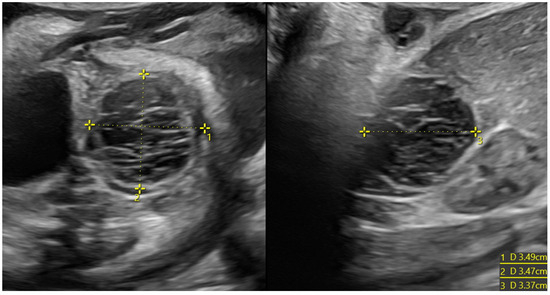

Figure 4. Ovarian cyst with hemorrhagic content in a female fetus at 33 weeks of pregnancy (3.5 cm of diameter). The formation did not regress, and a laparoscopic cystectomy was performed; at the histological examination, necrosis was reported.